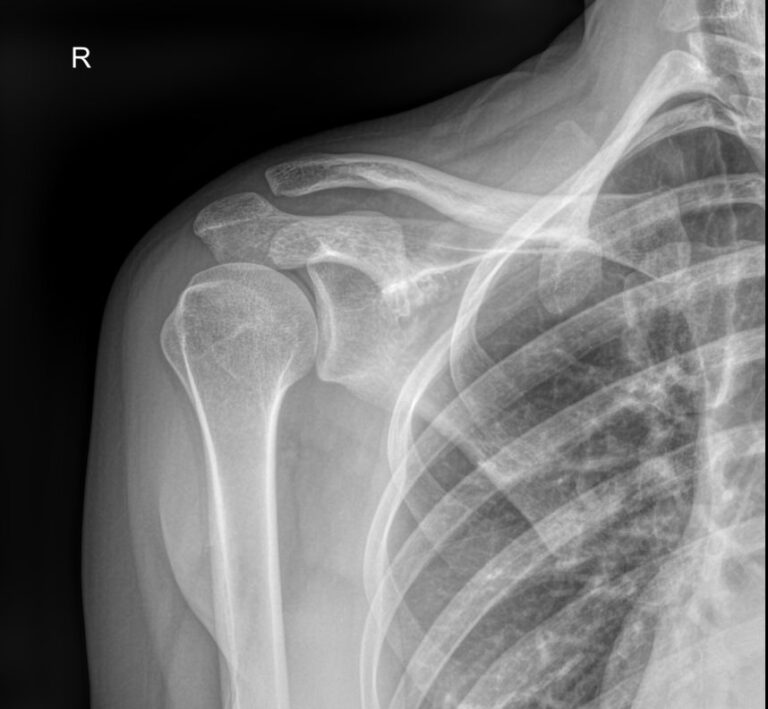

Плечевая кость ― одна из самых крепких в организме, что для ее повреждения требуется удар значительной силы. Переломы могут сопровождаться вывихами плечевого и локтевого суставов. Давно залеченная травма при неблагоприятных обстоятельствах может вызвать прерождение костной ткани.

Во всех случаях первичным методом диагностики будет рентгенография. Это простая и информативная процедура, которая не добавляет неприятных ощущений и быстро показывает полную картину патологии. Современное оборудование, которое используется в клинике «Доступная медицина», позволяет делать несколько снимков в течение короткого времени без опасности чрезмерного облучения.

Что покажет рентген плечевой кости

• Травматические повреждения, в том числе зажившие;

• Формирование костной мозоли;

• Патологические изменения костной ткани: разрежение, некроз, деструкция и другие;

• Состояние смежных суставов, вошедших в снимок;

• Опухоли и метастазы.